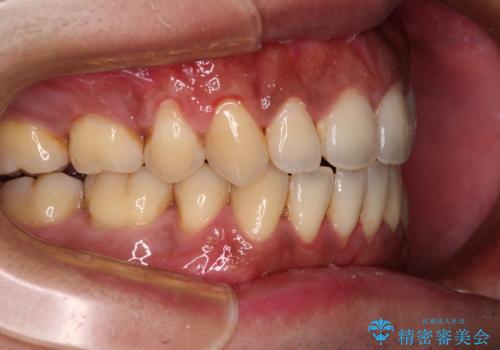

- 上下前歯の隙間と口元の出っ張った感じを気にして来院された患者様です。

上下の隙間は舌突出癖によるもので、またその癖により前歯が前方に出ている状態でした。

口元の出っ張りを改善するため、上下左右第一小臼歯4本を抜去し、ワイヤー装置にて矯正治療を行うこととしました。

舌の突出癖を改善するためのトレーニングを指導していましたが、なかなか改善することができず、ワイヤー装置を外してからも上下前歯に隙間ができやすい状況でした。